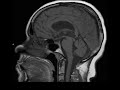

Pineal Gland Cyst

These images show a T1 hypointense, T2 hyperintense lesion in the posterior aspect of the third ventricle which appears to arise from the anterior aspect of the pineal gland. This lesion does not restrict diffusion or enhance and incomplete suppression on T2 FLAIR. The mass results in mild mass effect on the anterior aspect of the tectal plate and subsequently the cerebral aqueduct. There is mild supratentorial ventriculomegaly, but no evidence of transependymal flow as would be seen in acute obstructive hydrocephalus. Symptoms of a lesion in this location include Parinaud syndrome (vertical gaze palsy). Findings are most consistent with a pineal gland cyst. Differential considerations include pineocytoma (usually has solid enhancing components, but imaging features may overlap), arachnoid cyst (follows CSF on sequences), and epidermoid (should restrict diffusion).